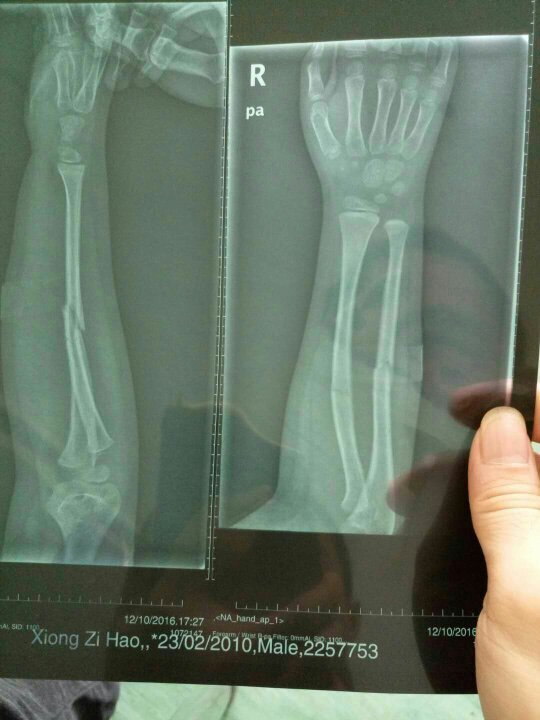

小孩在学校把右手摔断了,学校没派医生去了解情况,去找学校处理医费赔理问题,学校的回答是等出院了再说小孩在学校下课后到器材室去玩不小心把右手骨头给摔断了,当时学校也没第一时将小孩送往医院,而是先简单给小孩包扎之后打电话通知给家长,家长将小孩转了两次院后最后送往市儿童医院做手术,到医院两天了学校也没派人过问这件事,家长这边去找学校怎么处理医费赔偿问题,学校的回复是家长这边先垫付,等出院以后再说。现在家长这边当心出院后学校会不会耍赖,现在要不要通过司法程序,通过司法程序的话怎走